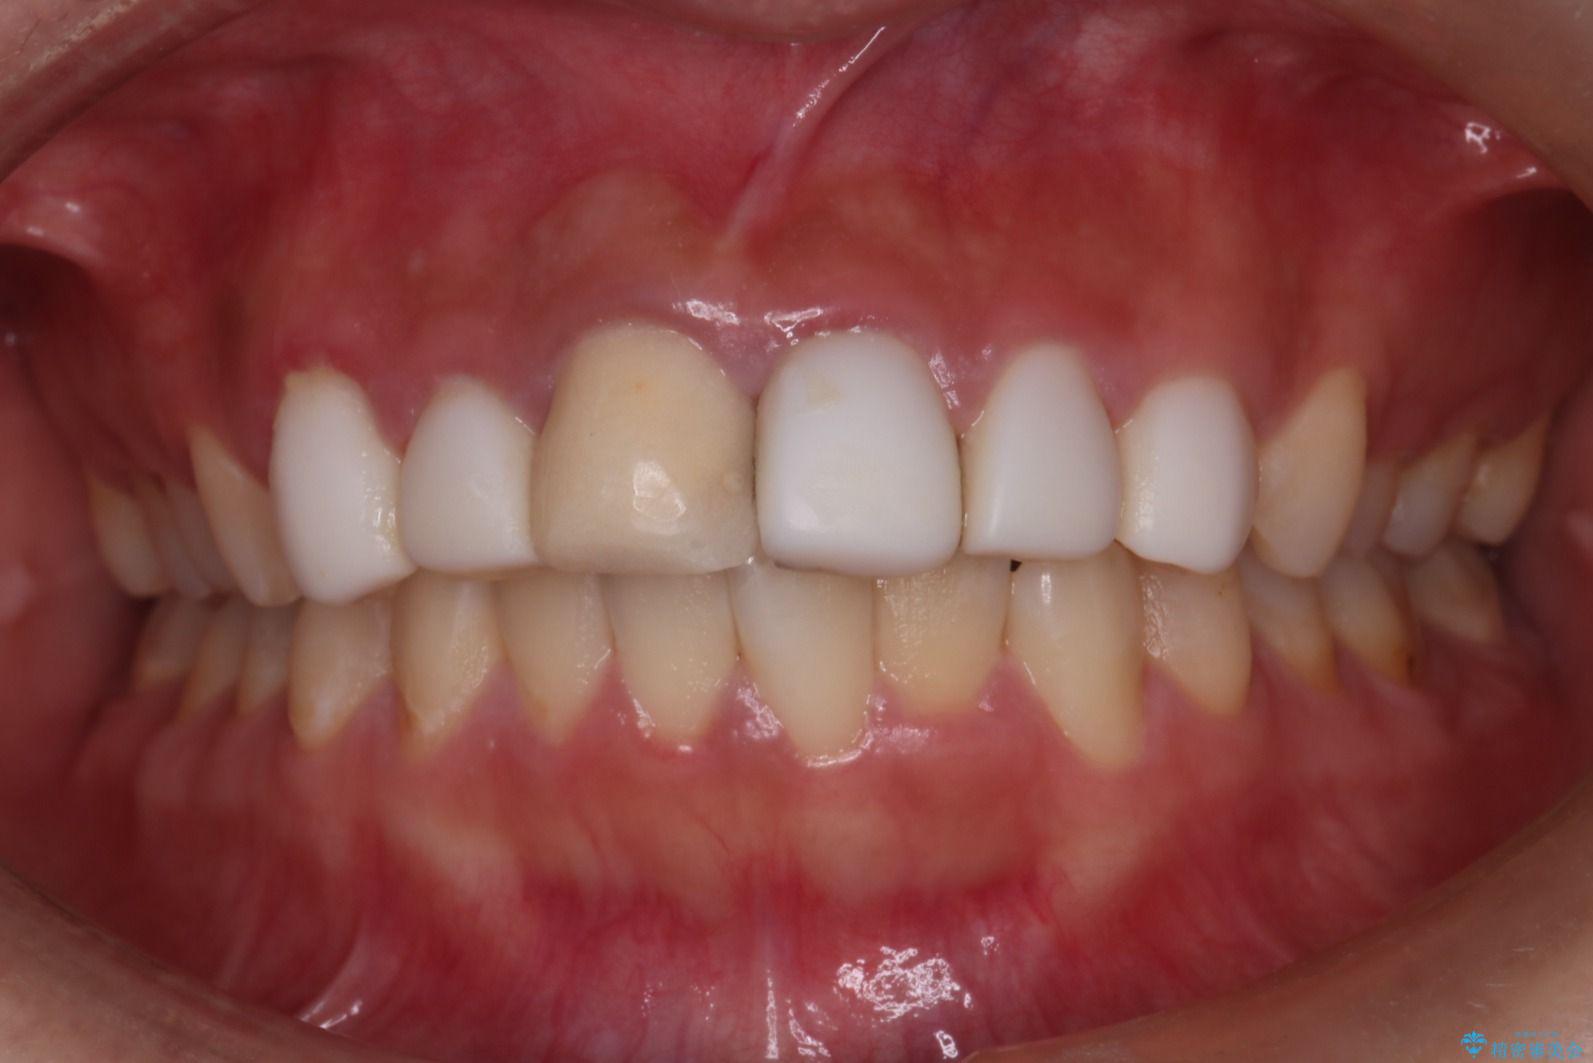

他院で治療した前歯の色が気になるとご来院された患者様です。

前歯の色に差があり、レントゲンで確認すると内部にう蝕も見られました。